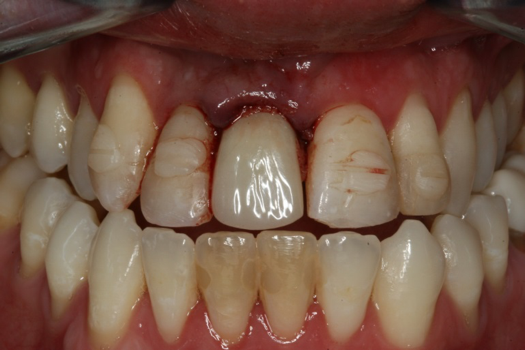

Fig 23. Provisional seated into position.

Figure 23

The provisional abutment and treatment crown were fabricated in the laboratory with the digital proposals. Platelet-rich fibrin (PRF) clot technology was incorporated to help with soft- and hard-tissue healing (Figure 19 through Figure 21). The screw-retained provisional and the PRF clot were seated immediately after implant placement (Figure 22 and Figure 23). One 4-0 polytetrafluoroethylene suture was placed to maintain papilla. The teeth immobilization splint was placed for 6 weeks (Figure 24). The rationale for splinting teeth Nos. 6 through 10 was due to noticeable plus-2 mobility of the remaining anterior teeth. The provisional implant crown also was included in the splint.

After 4 months of healing and integration of the bone around the implant, the digital workflow was initiated to develop the abutment and treatment plan. Another analog impression was made with an impression post and polyvinyl impression. The laboratory scanned the impression and digitized it to create the emergence profile of the milled titanium abutment and the final restoration (Figure 10 and Figure 11). The patient had a considerably thick soft-tissue profile, allowing a milled titanium abutment. The decision to use a titanium abutment was based on the patient's occlusion and propensity to fracture teeth or restorations. The virtual model was gray because the scanner does not recognize the color of the analog impression. The virtual final abutment and crown were approved and fabrication completed. The final restoration met the patient's esthetic values and his ability to function (Figure 12 and Figure 13).